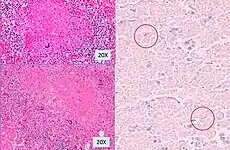

Histopathology, showing epithelioid granulomas with multinucleated giant cells and acid-fast bacilli -

One proposed mechanism is that tuberculous infection in the lungs results in erosion of the epithelial layer of alveolar cells and the spread of infection into a pulmonary vein.[10][11] Once the bacteria reach the left side of the heart and enter the systemic circulation, they may multiply and infect extrapulmonary organs.[11] Once infected, the cell-mediated immune response is activated. The infected sites become surrounded by macrophages, which form granuloma, giving the typical appearance of miliary tuberculosis.[12]

Miliary tuberculosis is a form of tuberculosis that is characterized by a wide dissemination into the human body and by the tiny size of the lesions (1–5 mm). Its name comes from a distinctive pattern seen on a chest radiograph of many tiny spots distributed throughout the lung fields with the appearance similar to millet seeds—thus the term "miliary" tuberculosis. Miliary TB may infect any number of organs, including the lungs, liver, and spleen.[5] Miliary tuberculosis is present in about 2 percent of all reported cases of tuberculosis and accounts for up to 20 percent of all extra-pulmonary tuberculosis cases.[6]